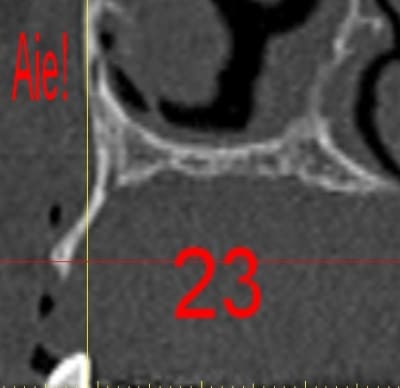

La première diapo est un essai pour justifier le concept (os non destiné à une utilisation greffe)

la deuxième est "tapée" dans une tête de femur de mauvais qualité (rejetée)

la troisième et suivante ce sont "les greffons" définitifs.

La précision 3D du scan est elle suffisante pour une adaptation passive sur l'os réel ?

La tu nous montres sur un stereolitique obtenu à partir du scan, ok ça colle mais en bouche ?

mais ce n'est pas la seule raison, en effet il me semble que le risque de contamination croisée est important lors de la mise en forme directement en bouche et de la taille au moteur.

Or, une des qualité de l'os fourni par BIOBANK, c'est la préparation (CO2 supercritique et divers), donc il me semble dommage de "polluer" ça en ajustant la pièce.